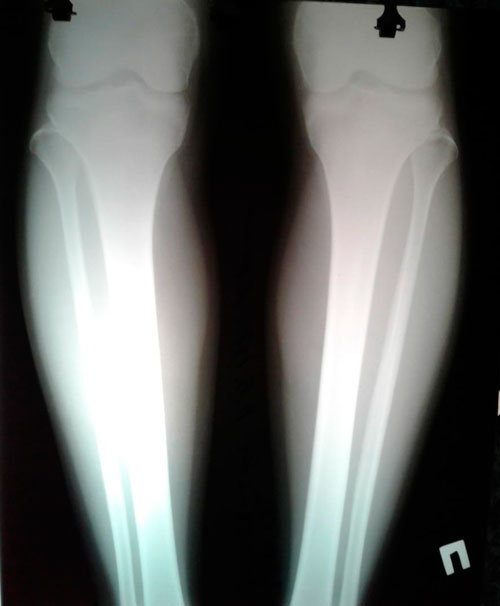

Исходник - 32 года. Атырау.

Дата операции - 26.01.2019.

Дата операции - 26.01.2019г.

Дата снятия аппаратов - 31.05.2019г.

Срок сращени - 120 дней.